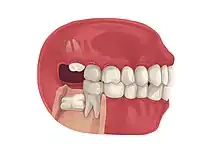

Impacted wisdom teeth is a condition where the third molars (wisdom teeth) are prevented from erupting into the mouth.[1] This can be caused by a physical barrier, such as other teeth, or when the tooth is angled away from a vertical position.[2] Completely unerupted wisdom teeth usually result in no symptoms, although they can sometimes develop cysts or neoplasms. Partially erupted wisdom teeth can develop cavities or pericoronitis. Removal of impacted wisdom teeth is advised in the case of certain pathologies, such as nonrestorable caries or cysts.[3]

Wisdom teeth become impacted when there is not enough room in the jaws to allow for all of the teeth to erupt into the mouth. Because the wisdom teeth are the last to erupt, due to insufficient room in the jaws to accommodate more teeth, the wisdom teeth become stuck in the jaws, i.e., impacted. There is a genetic predisposition to tooth impaction. Genetics plays an important, albeit unpredictable role in dictating jaw and tooth size and tooth eruption potential of the teeth. Some also believe that there is an evolutionary decrease in jaw size due to softer modern diets that are more refined and less coarse than our ancestors'.[6]